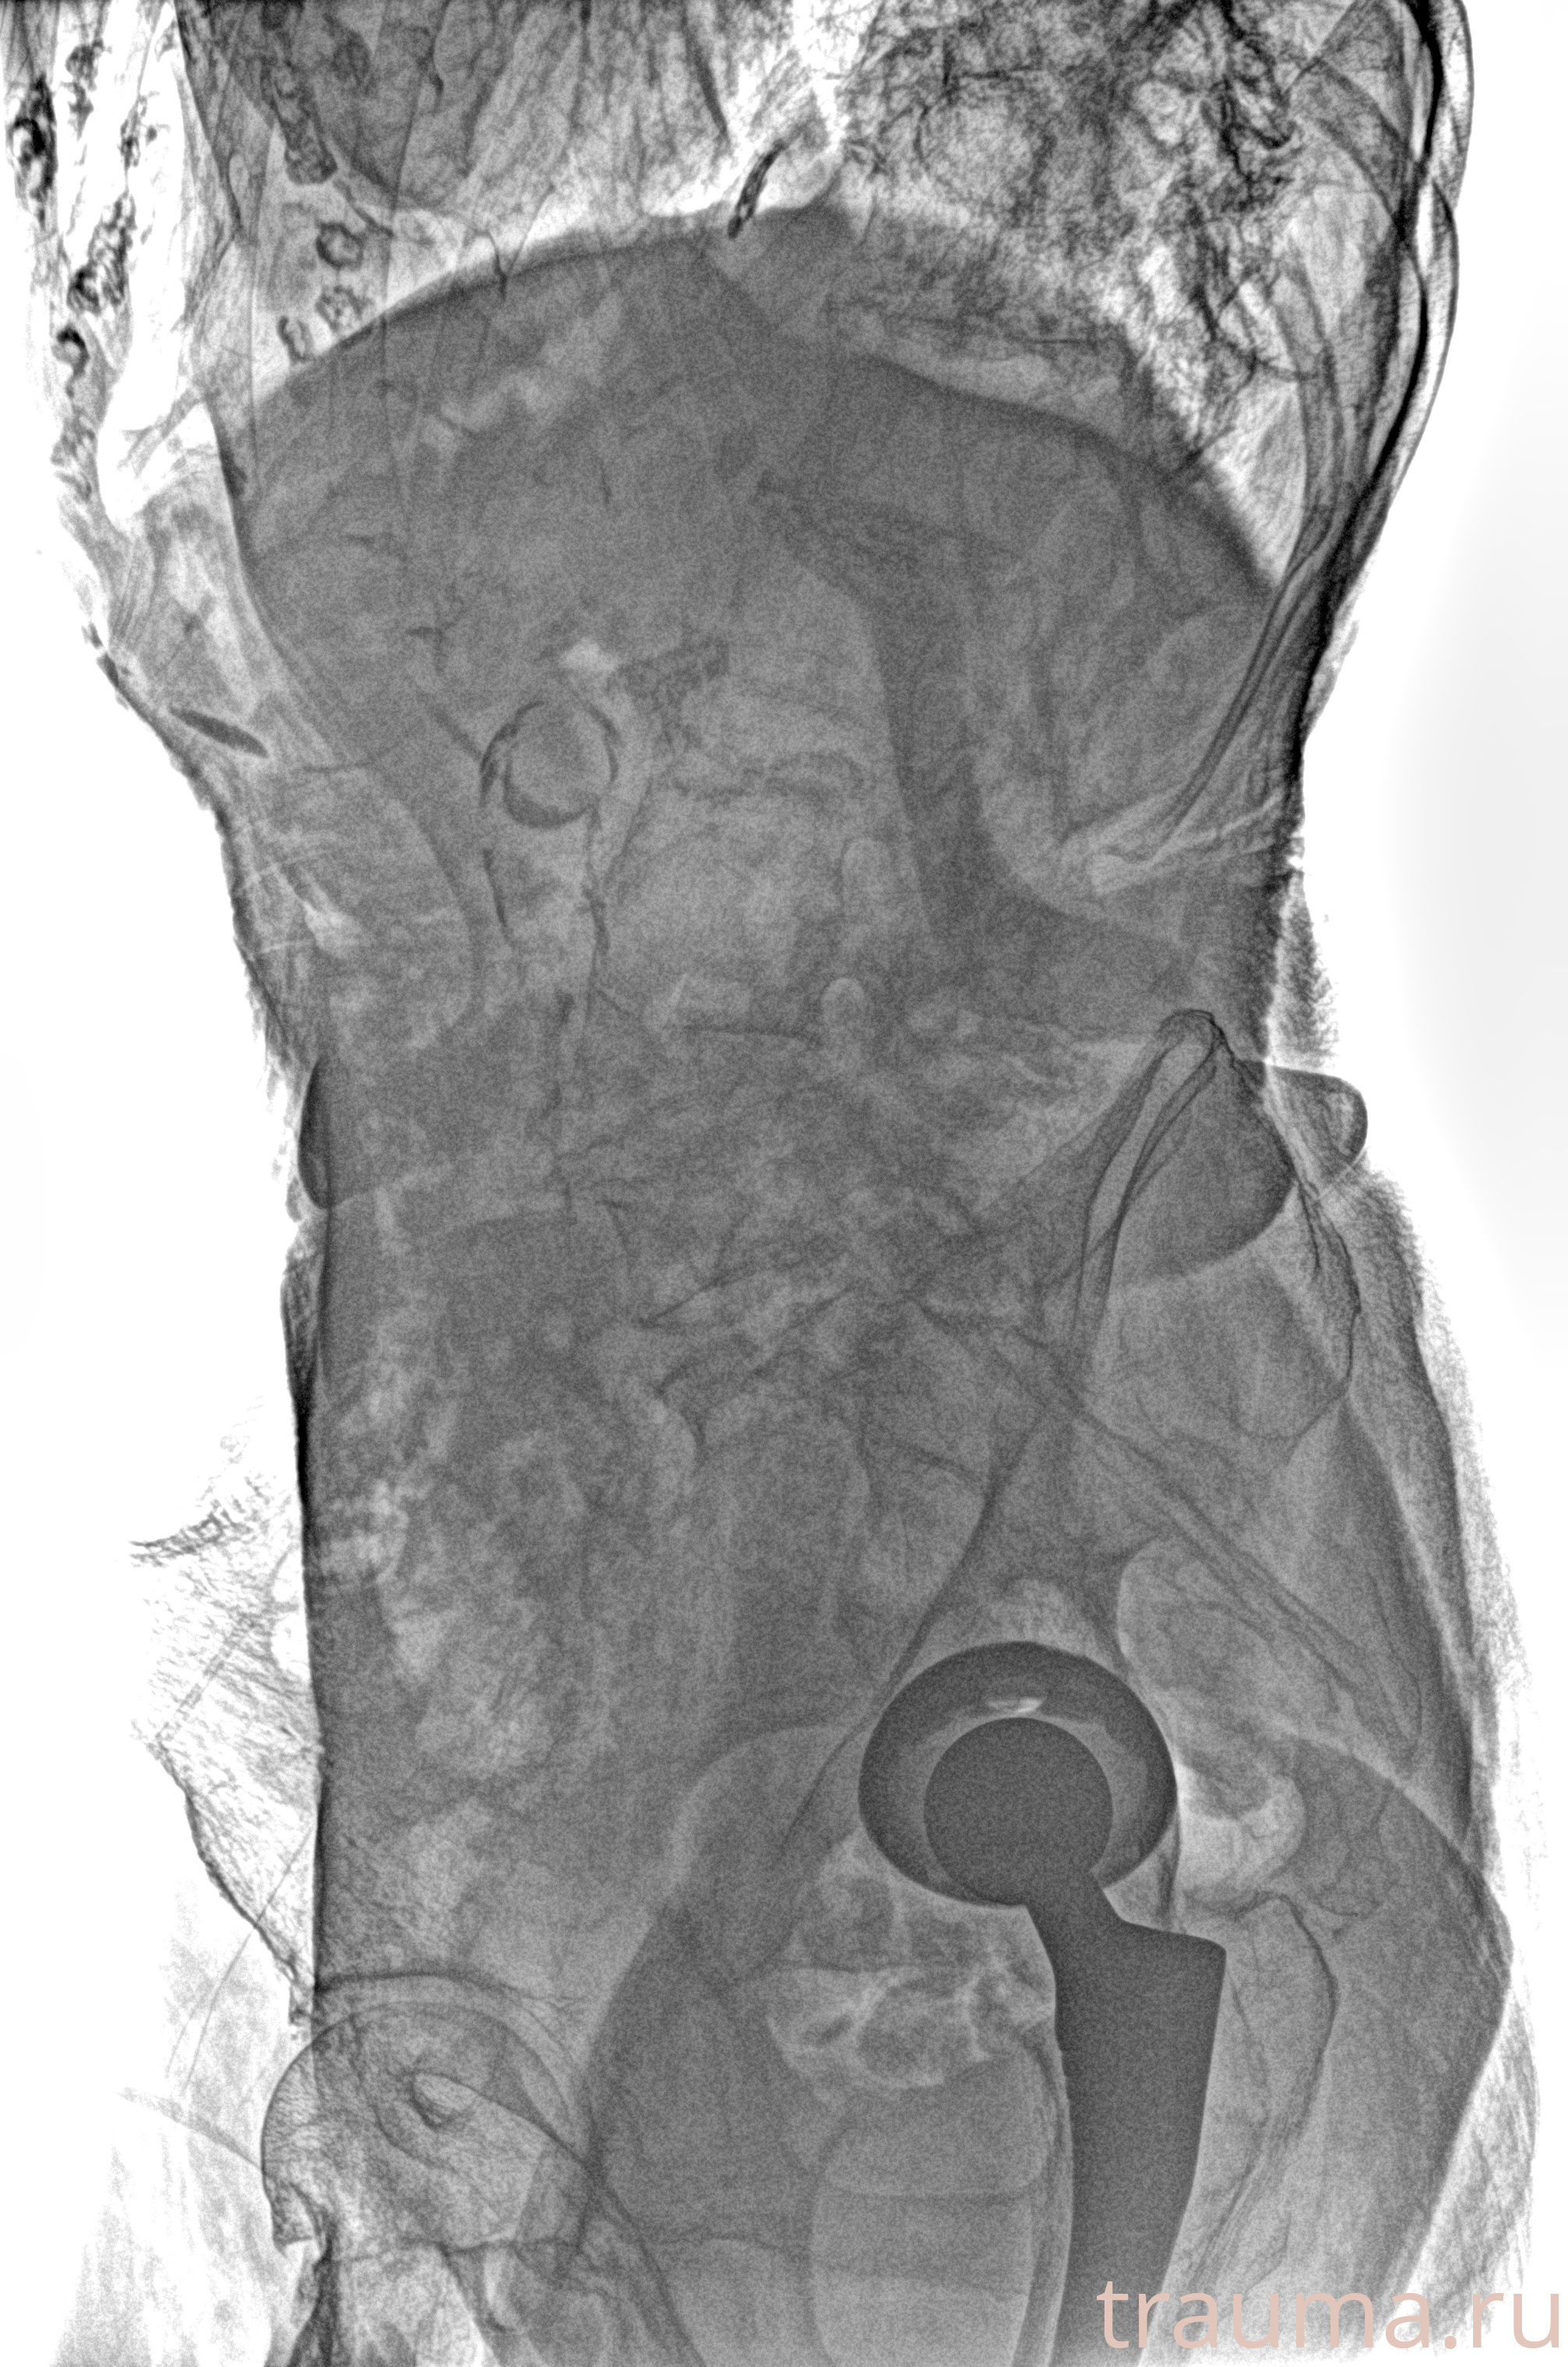

Рентген на дому: по вашему адресу приезжает врач-рентгенолог, травматолог-ортопед с мобильным рентгеновским аппаратом, проводит диагностику травмы или заболевания, делает необходимые рентгенограммы, дает рекомендации по дальнейшему лечению. Получить качественные снимки в домашних условиях возможно благодаря уникальной методике, разработанной МосРентген Центром для института  Склифосовского